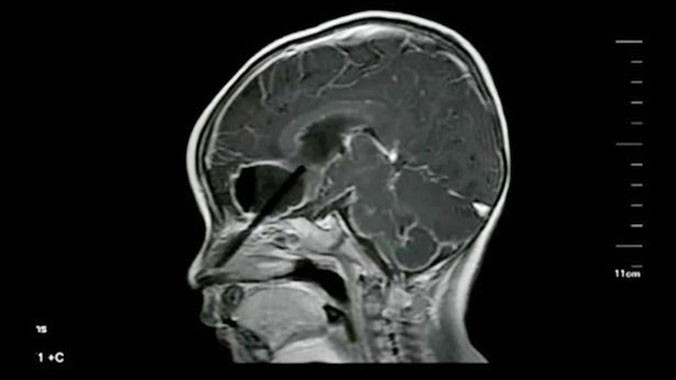

Ảnh chụp X-Quang đoạn đũa mắc trong não cậu bé.

Một em bé người Trung Quốc đã sống sót một cách thần kỳ khi bị đoạn đũa dài 6cm mắc kẹt trong đầu suốt 10 ngày liền.

Sau khi rút đoạn đũa mắc trong mũi Hanghang, bố mẹ cậu bé đã đưa cậu đến bệnh viện để kiểm tra và rửa vết thương. Tuy nhiên cả bố mẹ Hanghang lẫn các y bác sĩ đều không hề hay biết rằng vẫn còn một đoạn đũa dài 6 cm mắc kẹt trong não bé.

Trở về nhà, Hanghang có triệu chứng bị nôn mửa và bố mẹ đưa cậu bé quay trở lại bệnh viện để kiểm tra lại. Lần này, tất cả mọi người đều phát hoảng khi tìm thấy đoạn đũa còn lại mắc trong đầu cậu bé.

Rất may là nó mắc trong khu vực không có chức năng hoạt động của não. Sau khi lấy đoạn đũa dài 6cm còn lại ra, sức khỏe cậu bé được cải thiện rõ rệt. Tuy nhiên, cậu bé bị nhiễm trùng não và phải ở lại bệnh viện để điều trị thêm.”